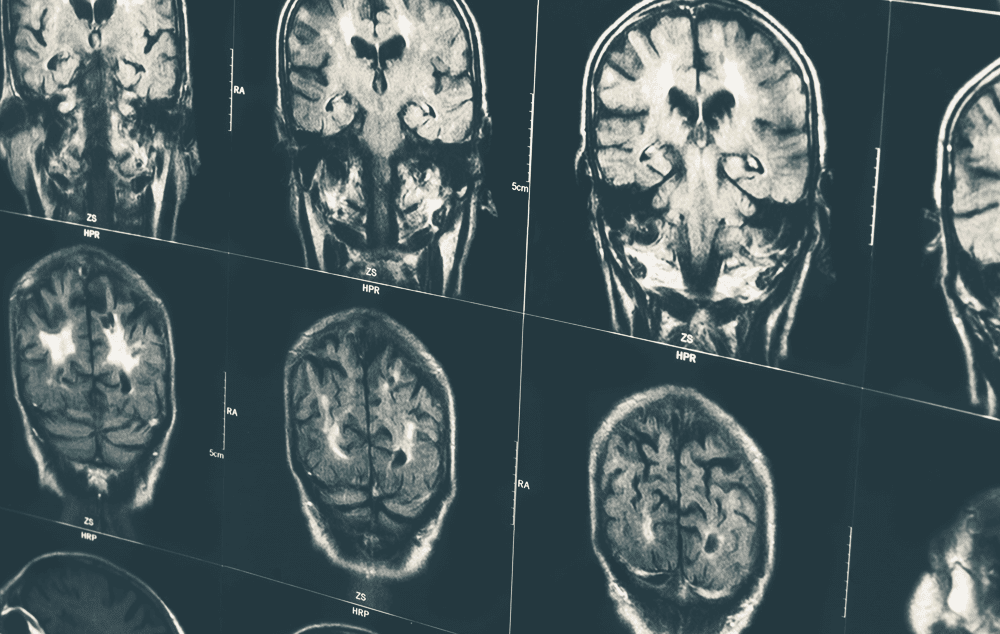

A ressonância magnética é considerada um dos maiores avanços do século em diagnóstico médico por imagem. Trata-se de um exame de diagnóstico por imagem que não utiliza radiação, mas sim um campo magnético que permite gerar imagens de alta definição e com maior exatidão do crânio.  Para realiza-lo, é importante não utilizar joias, maquiagem, entre outros acessórios, em razão do magnetismo. O tempo de realização pode durar até uma hora.